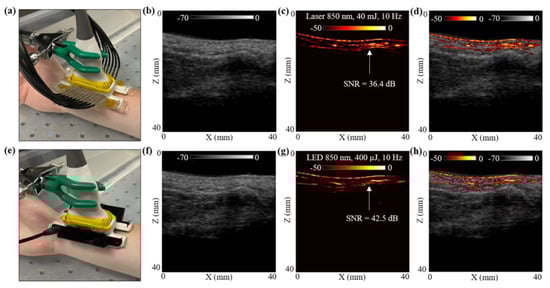

Figure 5.

In vivo comparison of LED array-based and laser-based PA vasculature imaging over the right-hand wrist of a healthy 25-year-old male human volunteer. (a) Shows the experimental setup with the right-hand wrist placed inside a big water bath for the laser-based PA imaging. (b–d) Show the obtained US, PA and coregistered US + PA images for the setup shown in (a). (e) Shows the setup with LED arrays. (f–h) Show the obtained US, PA, and coregistered US + PA images for the setup shown in (e).

The hand was first imaged with the laser-PAUS setup by attaching the laser fiber holders to the US probe, as shown in Figure 5a. The laser was operated at 850 nm wavelength, 10 Hz PRF, and delivered output optical energy of 40 mJ. This allowed ANSI safety limits of <20 mJ/cm2 optical fluence on the hand surface [59]. During the real-time data acquisition, the probe was aligned such that the major blood vessel could be seen running parallel to the skin surface in the PA images. The captured US and PA raw data using the AcousticX software were later extracted in the MATLAB software and were reconstructed to generate the beamformed images. The beamformed, log-compressed B-mode US, PA and the coregistered US + PA images are shown in Figure 5b–d. The US image showed the anatomical features along the depth of human wrist, whereas the PA image highlighted the major blood vasculature. There was fairly strong correspondence between the locations of the blood vessel in the PA image and the appearance of anechoic regions in the US image. Based on the anatomy of the vasculature in human wrist, the PA signals ~5 mm below the skin surface may have corresponded to the radial artery that travels across the front of the elbow, deep under the muscle until it comes to the wrist where it comes close to the skin surface. This is also marked with a white arrow in the PA image in Figure 5c.

To compare these laser-illumination results of the human wrist with the LED arrays, the laser-fiber attachments were gently removed without disturbing the location of the US probe. The two 850 nm LED arrays were then attached to the US probe, as shown in Figure 5e. With a PRF of 4 KHz and frame averaging of 384, leading to a frame rate of 10 Hz, the US and PA frames were captured using the LED array setup. The US and PA raw data were then reconstructed in MATLAB. Figure 5f–h show the beamformed log-compressed B-mode US, PA and coregistered US + PA images for the human wrist. As in the case of laser illumination, the LED array-based PA images also imaged the same vasculature below the skin surface. The radial artery present ~5 mm below the skin was clearly visible with the LED array-based acquisition as well.

To further compare the two setups quantitatively, an SNR comparison study was performed for the radial artery, as marked with white arrows in Figure 5c,g. To calculate the SNR, the peak PA signal at the artery and the mean noise adjacent to the artery region was calculated over the linear beamformed PA images resulting from the laser-illumination and the LED array-based acquisitions. Table 3 presents the values of peak PA signal, mean noise and the SNR. The SNR values are also marked in the Figure 5c,g. Both the peak signal and mean noise with the laser are up to three log orders of magnitude higher compared to the LEDs. However, the SNR value for the laser-illumination-based PA image was about 6 dB lower than the SNR with the LED array acquisition. This follows the trend observed for the controlled tissue phantom studies discussed in Section 3.1, where the shallow targets (<30 mm) inside an intralipid medium were detected with higher SNRs using LED arrays compared to the laser illumination, maintaining the same frame rate.

In the final study, in Section 3.4 we presented an in vivo LED-PAUS and laser-PAUS imaging of the wrist of a healthy human volunteer. Figure 5 presents the qualitative and quantitative comparison results for a radial artery seen ~5 mm below the wrist skin surface. Analysis of the peak PA signal, mean noise and SNR for this radial artery is presented in Table 3. As observed with the studies presented in previous sections, for a shallow depth target, the LED-PAUS showed better SNR than the laser-PAUS at the same 10 Hz frame rates. The ~5 mm deep radial artery was imaged with a 36.37 dB SNR with the laser compared to a 42.49 dB SNR with LED arrays. This study substantiates that the LED-PAUS imaging is an attractive choice for several preclinical and clinical applications.